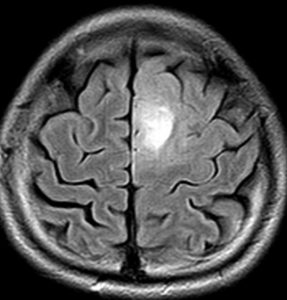

MRIでみえる腫瘍の領域を腫瘍体積 (GTV)といいます

これは退形成性星細胞腫グレード3のフレア画像と言います。白く見える部分が腫瘍なのですが,どこまでが腫瘍なのかMRIでもわかりにくいものです